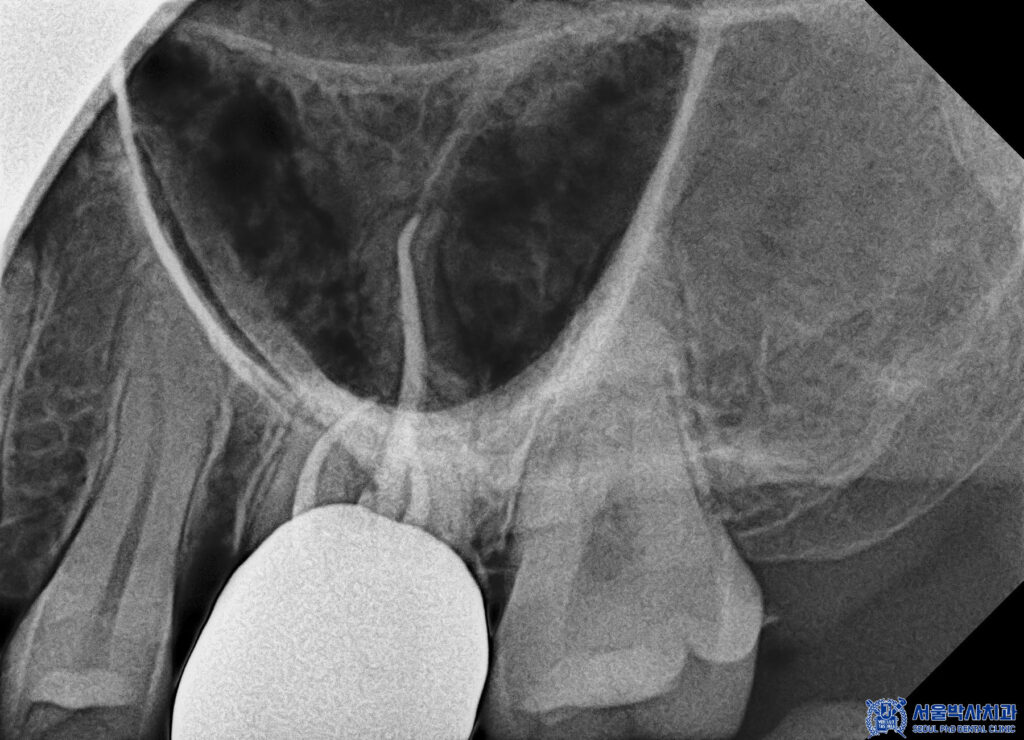

CT상에서도 뿌리 끝 부위에

염증 병소가 보다

명확하게 확인되었습니다.

파노라마에서는 평면적으로 보였다면,

CT 촬영을 통해 염증의 위치와 범위,

주변 뼈 손상 정도까지

입체적으로 확인할 수 있었고,

그 결과 해당 치아는 신경치료가

필요한 상태임을 판단할 수 있었습니다.